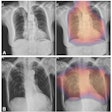

(A) Chest x-ray unaided by the AI system. (B) Chest x-ray aided by the AI system shows two Lung ROIs (green boxes) and a Mediastinum/Hila ROI (yellow box). The AI system identified abnormalities that were characterized as regions of interest in Lungs and Mediastinum/Hila. The abnormalities were bilateral upper lobe pulmonary fibrosis (categorized as ‘Lungs’), and pulmonary artery hypertension along with bilateral hilar retraction (categorized as ‘Mediastinum/Hila’). The ROIs for each category are illustrated in different colors for readability.Image available for republishing under Creative Commons license (CC BY 4.0 DEED, Attribution 4.0 International) and courtesy of Scientific Reports.